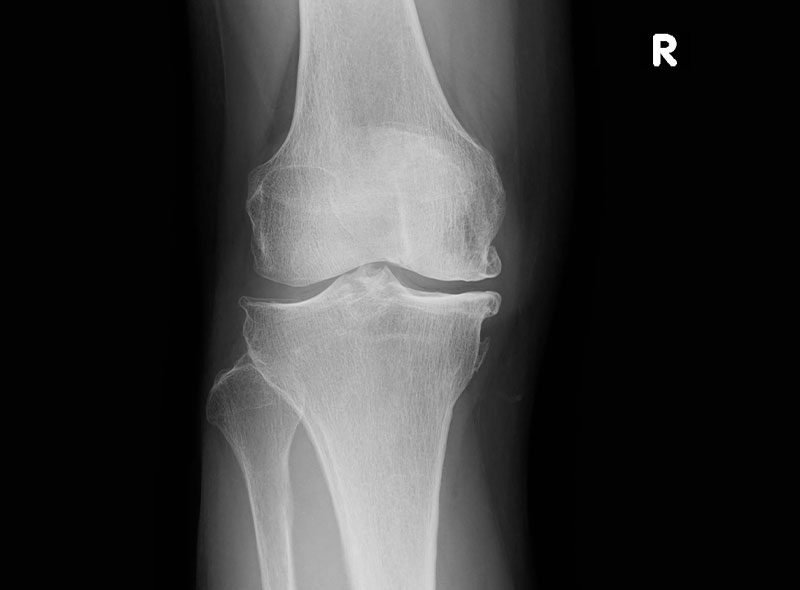

レントゲンや超音波診断も有効です。